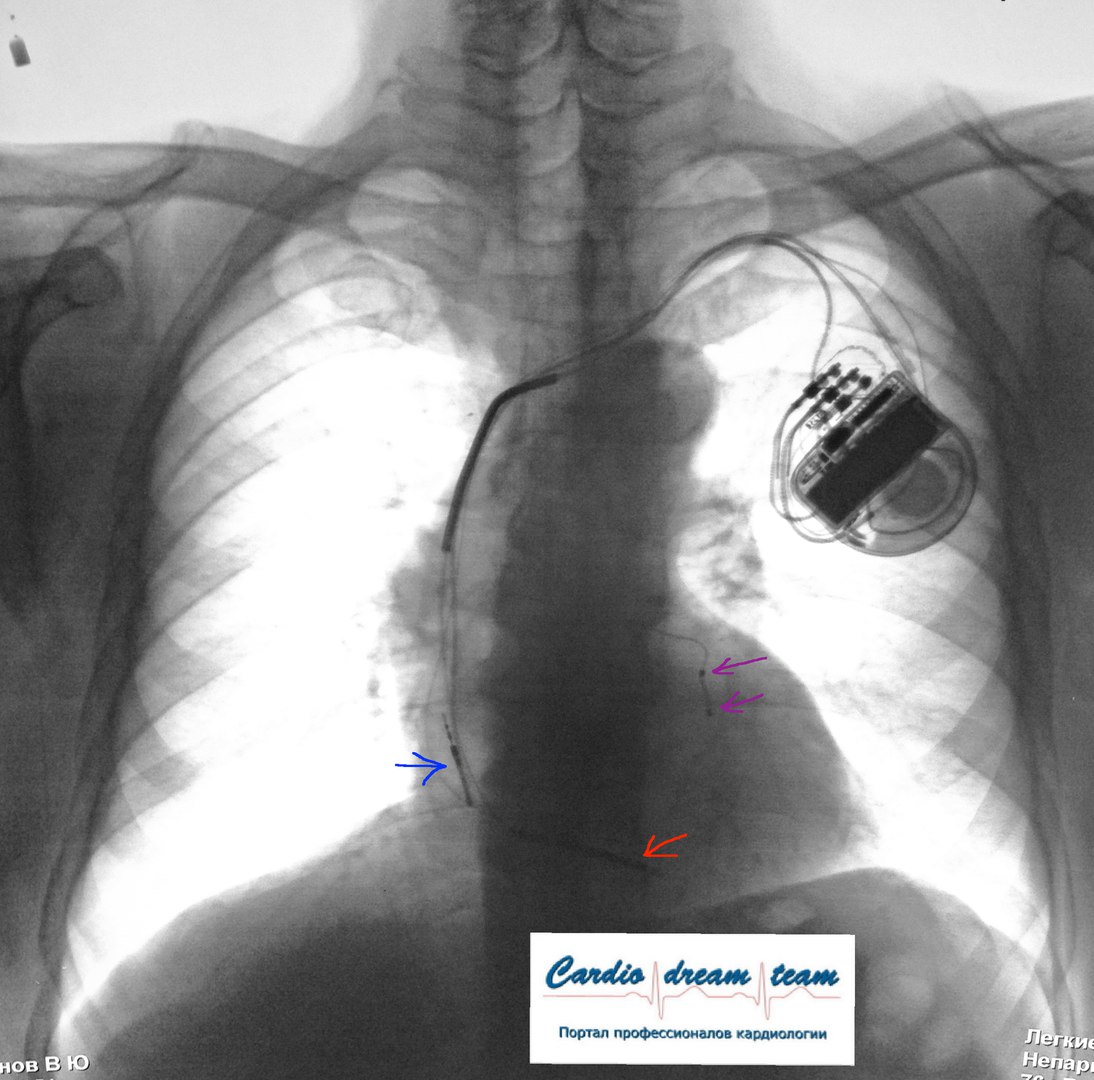

ИКД + RCT на рентгене. Синий - предсердный электрод. Сиреневые желудочковые для синхронизации. Красный электрод для дефибрилляции. Всё на месте.

ИКД + ЭКС DDD. Когда всё на месте и всё работает.